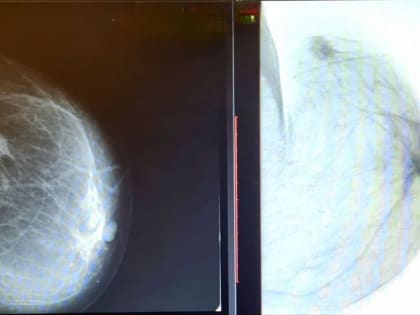

В горбольнице №5 показали то, чего боится каждая женщина

Со 2 по 8 октября в России проводится неделя борьбы с раком молочной железы.